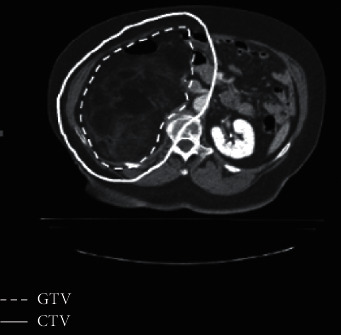

Results: CTVs ranged from 74 to 357 cc (mean 188 cc). Dose conformity was improved with IMPT, while 3D CPT provided better dose homogeneity. Mean dose to the liver, small bowel, and stomach was reduced with IMPT compared with 3D CPT or IMXT.

Conclusions: IMPT, 3D CPT, and IMXT provide excellent target coverage for retroperitoneal sarcomas. OAR dose is lower with IMPT and 3D CPT, and IMPT achieves the closest conformity. These techniques offer the opportunity for further dose escalation to areas with positive margins.